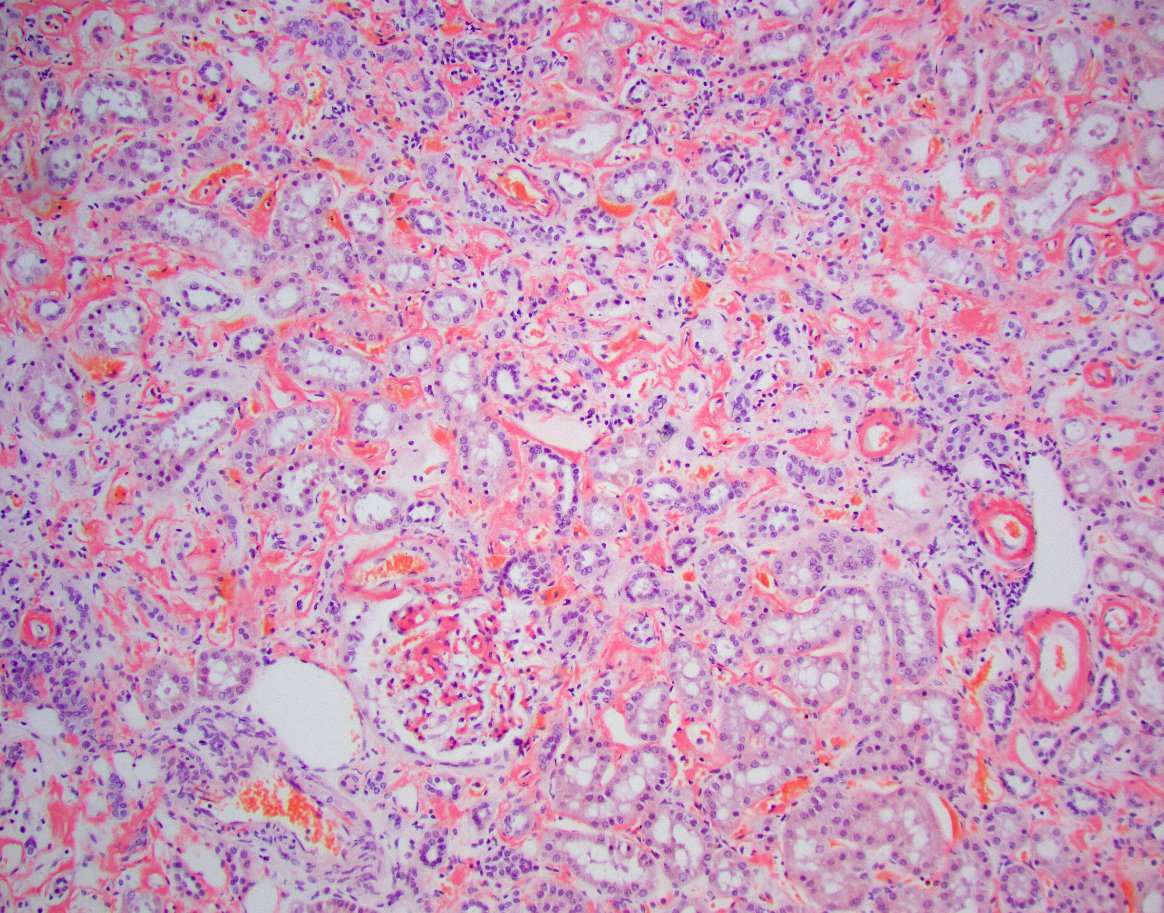

"The Banff 2024 Kidney Meeting Report: Rejection as a spectrum of phenotypes and focus on differential diagnostic reasoning," Naesens et al.